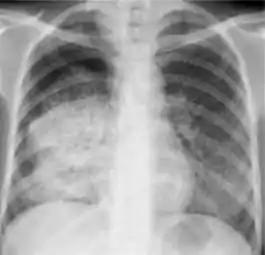

Chest x-ray showing coarse reticulonodular densities on the lower right lung of post-primary pulmonary TB.